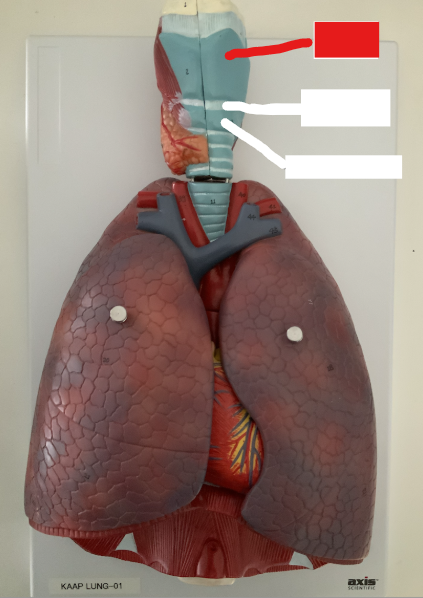

Trachea

What structure is this?

Tracheal Cartilage

What structure is this?

Cardiac Notch

What structure is this?

Superior lobe of the left lung

What structure is this?

Inferior lobe of the left lung

What structure is this?

Superior Lobe of the right lung

What structure is this?

Middle lobe of the right lung

What structure is this?

Inferior lobe of the right lung

What structure is this?

Left lung

What structure is this?

Right lung

What structure is this?

Right main bronchus

What structure is this?

Right superior lobar bronchus

What structure is this?

Middle Lobar bronchus

What structure is this?

Right inferior lobar bronchus

What structure is this?

Left main bronchus

What structure is this?

Left superior lobar bronchus

What structure is this?

Left inferior lobar bronchus

What structure is this?

The carina

The pharynx

Larynx

What are the three laryngeal cartilages?

epiglottis, cricoid and thyroid cartilage

Horizontal fissure of right lung

What structure is this?

Oblique fissure of right lung

What structure is this?

Oblique fissure of left lung